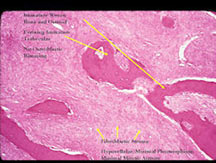

Microscopic Pathology